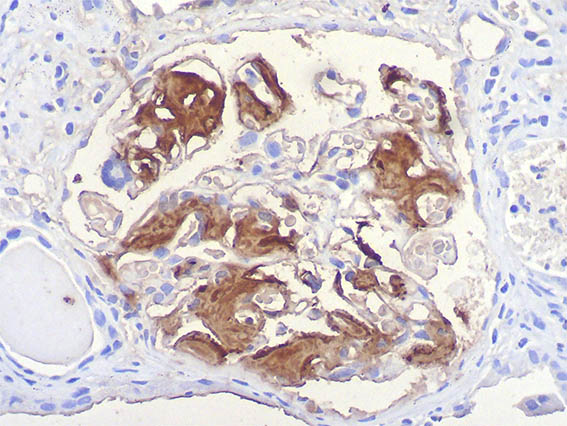

Figura 13. Inmunotinción para amiloide A, X400.

Figura 14. Inmunotinción para amiloide A, X400.